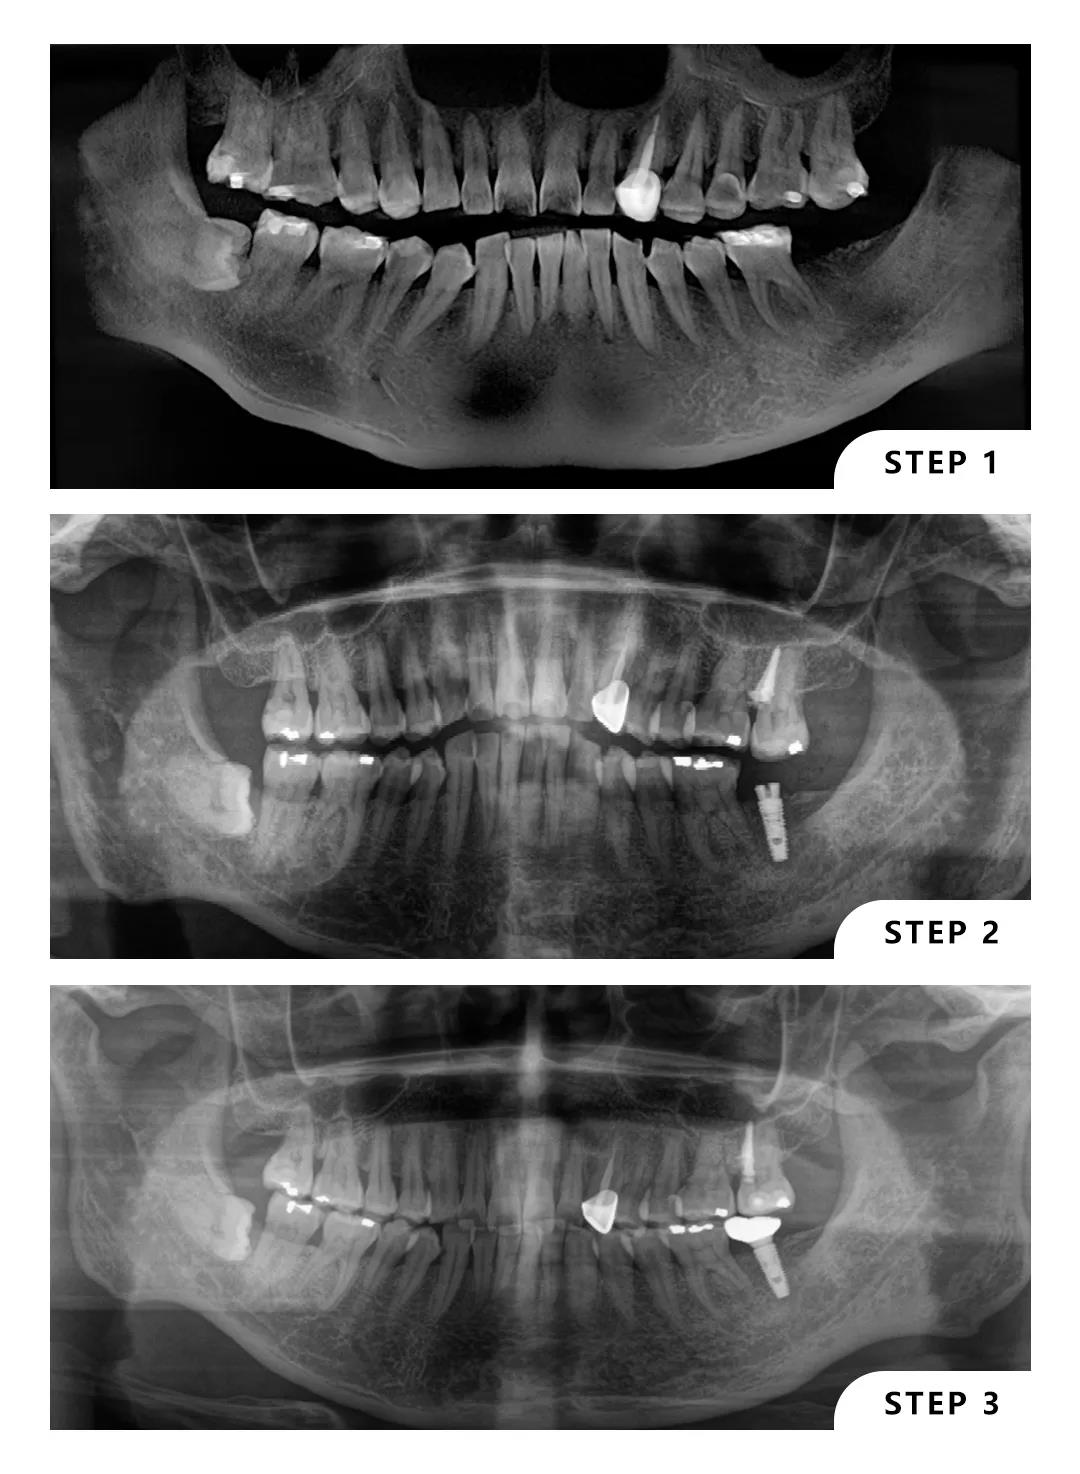

这位患者左下7缺失,左上7伸长,患者本人可以接受种植,但不接受磨牙。

曹医生在面诊后给出了左上7向上牵引,左下7种植的方案,经过一年的努力,患者对效果很满意。